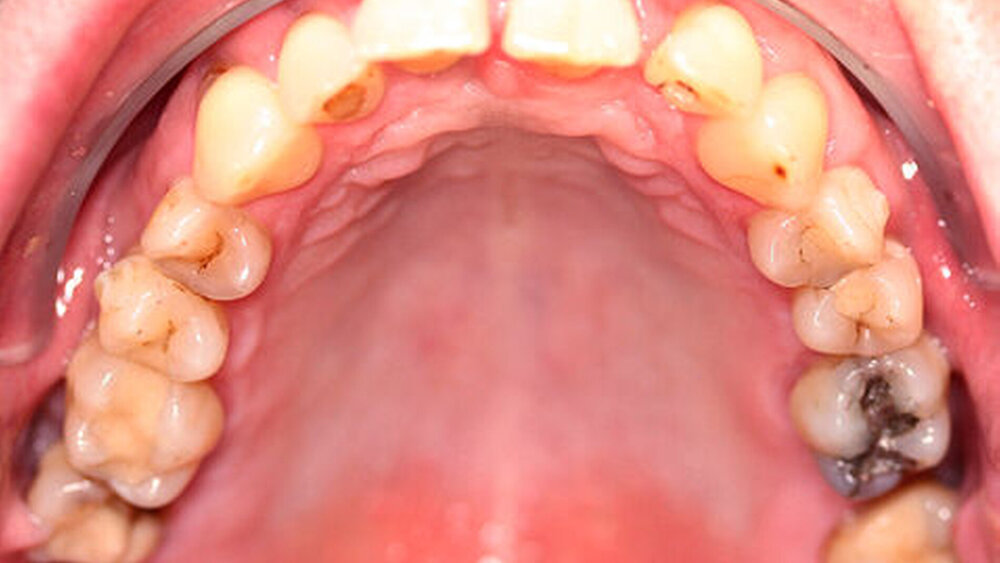

Anamnestisch lagen keine Besonderheiten vor. Es ist jedoch zu vermerken, dass ein regelmäßiger Alkohol-, Koffein- und Nikotinkonsum zugrunde lag. Intraoral zeigte sich ein bereits konservierend versorgtes permanentes Gebiss mit aktivem und inaktivem kariösen Geschehen. Große Anteile der Zahnhälse lagen nach Zahnfleischrückgang in Kombination mit Knocheneinbrüchen frei. Zahn 27 wurde bereits extrahiert.

Röntgenologisch stellte sich im Orthopantomogramm der bereits intraoral ersichtliche horizontale und vertikale Knochenabbau mit Attachmentverlust an einzelnen Zähnen dar. Die Erhaltungswürdigkeit einzelner Zähne war aufgrund des starken Knochenverlustes beziehungsweise der Beeinträchtigung des Halteapparates als kritisch zu beurteilen.

Zudem wurde die Diagnose einer Parodontitis gestellt, die eine Rücküberweisung an den Hauszahnarzt erforderlich machte (Abbildung 2).